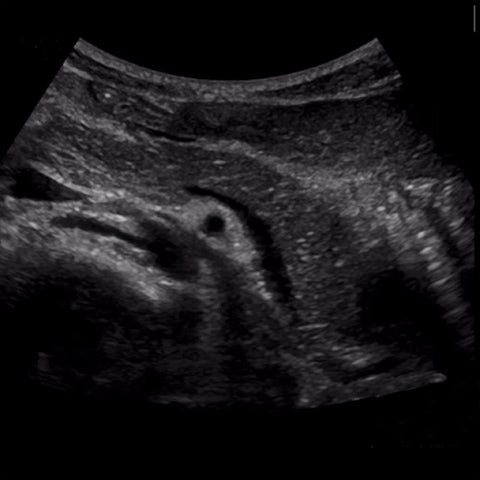

Today we are thankful for clearly visualized pancreas .We can give you visual instruction.